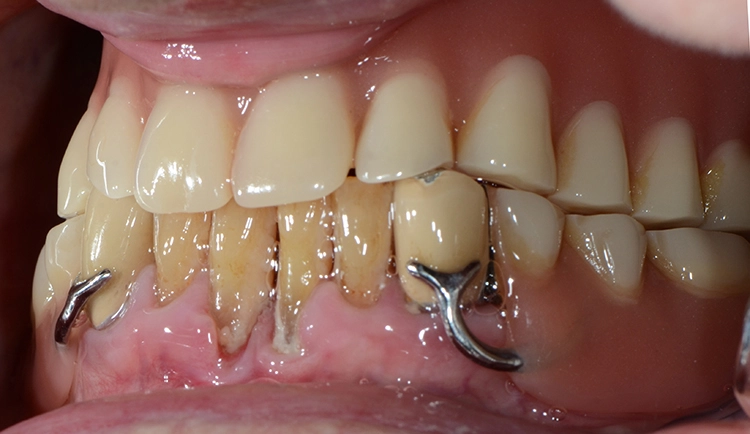

Bei den meisten alltäglichen Tätigkeiten wie Körperpflege und Kochen gaben die 100-Jährigen an, Hilfe zu benötigen. Obwohl offensichtliche Defizite in der häuslichen Mundhygiene vorlagen, wie generalisiert harte und weiche Beläge, schlecht gereinigter herausnehmbarer Zahnersatz, Druckstellen usw., gaben nur 7 (12,7%) der 100-Jährigen an, hierbei Hilfe zu benötigen. Die Abbildungen 1 bis 3 zeigen beispielhaft die klinische intraorale Situation von 3 100-Jährigen, die an der Untersuchung teilgenommen haben.